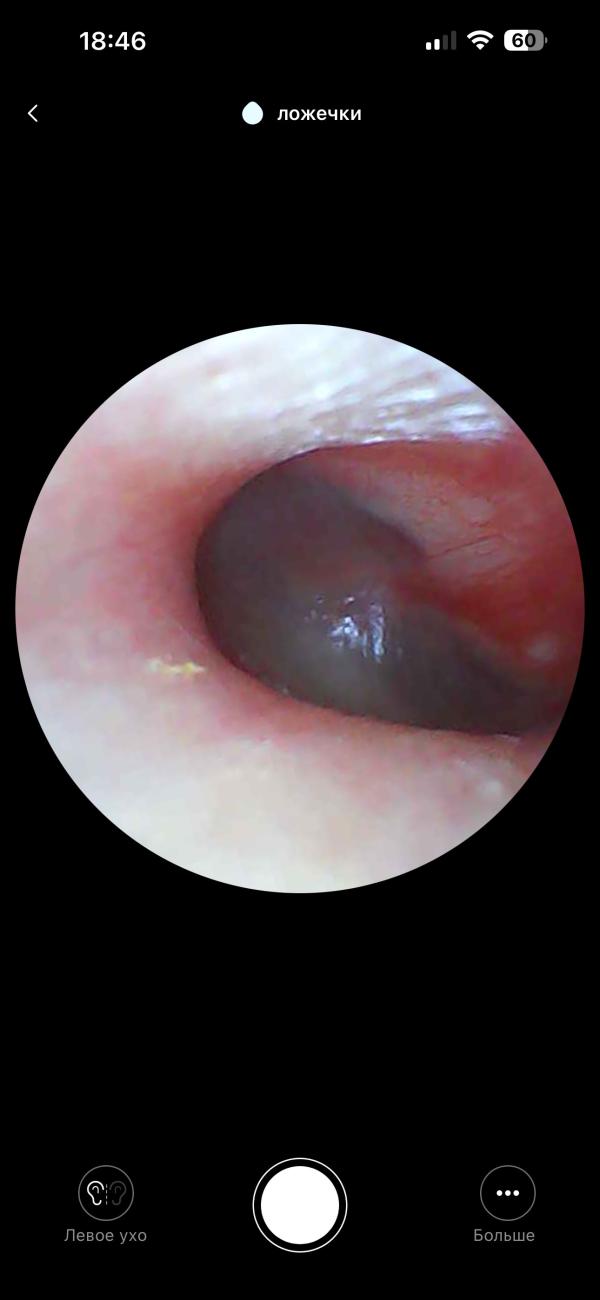

post image 1

Кто знает, это отит?(((( подскажите плиз 😢

У нас такое было , врач показывал на экране , был отит 2 степени

Я не врач, но я тоже так смотрю. Перепонка не повреждена, а снаружи краснота, значит отипакс лишним не будет и не навредит

@bakaeva_krg да, когда такая картина у сына, врач обычно пишет наружный средний отит